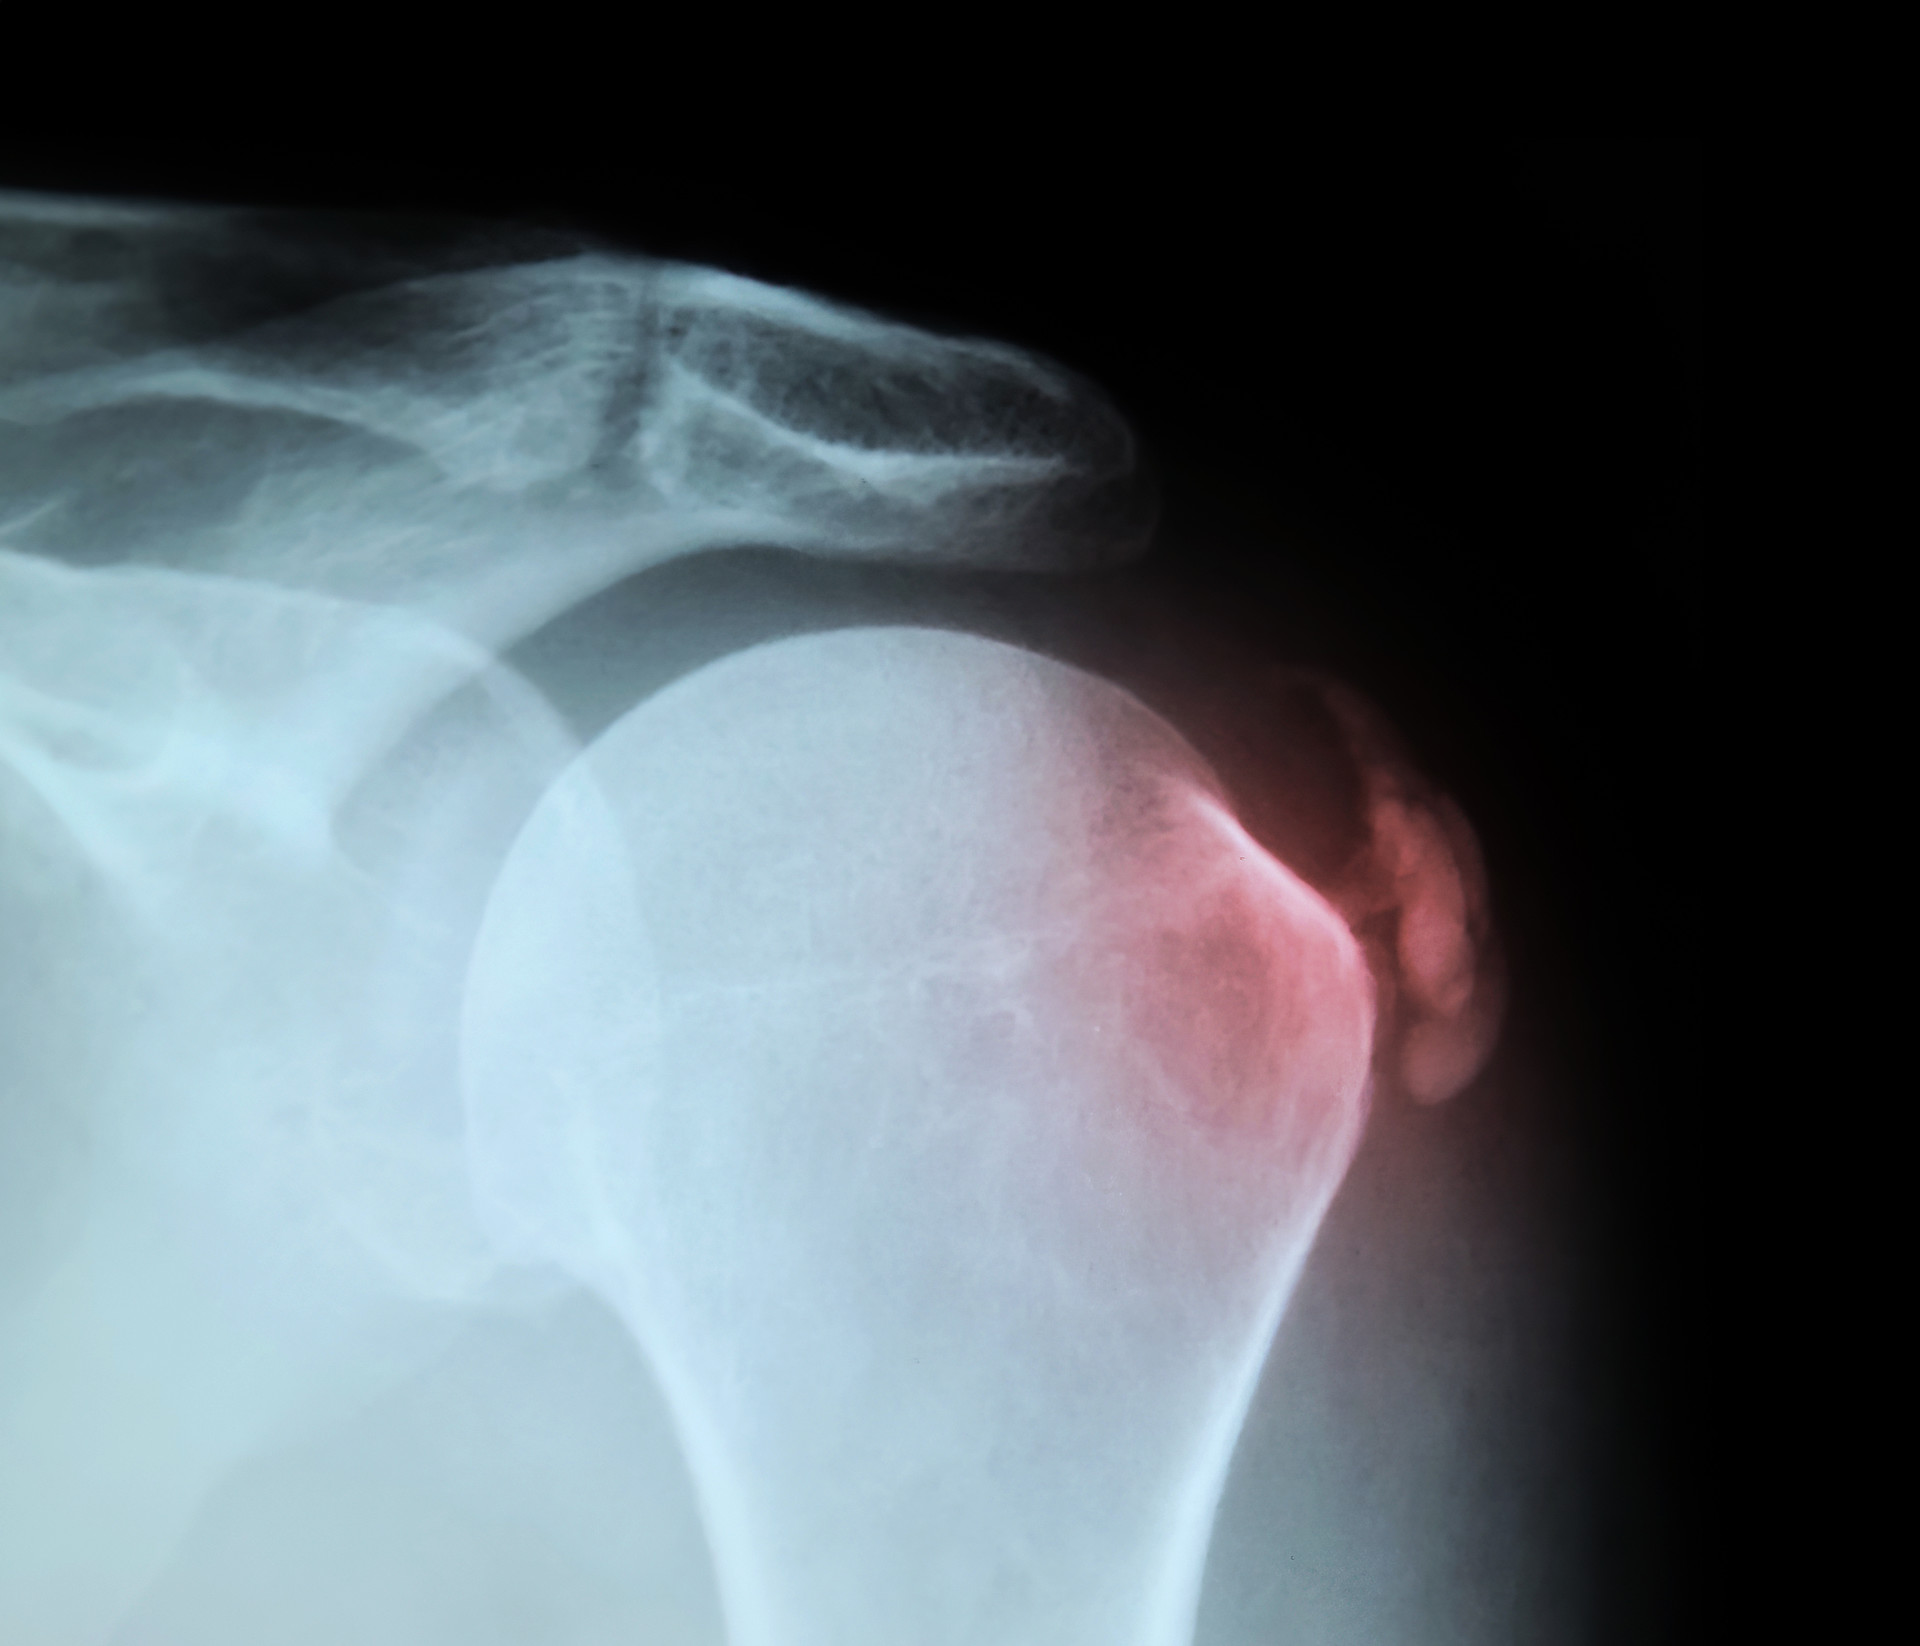

어깨 힘줄(회전근개)에 칼슘성 석회가 침착되어

염증과 극심한 통증이 발생하는 질환입니다.

X‑ray로 쉽게 식별 가능하며, 주로 어깨 힘줄에서 잘 생기지만

드물게 엉덩이나 무릎, 손목 같은 다른 힘줄에서도

발생할 수 있습니다. 흔히 50~80세에 발병하지만

최근엔 젊은 층에서도 증가 추세가 나타나고 있습니다.

X-Ray로 석회의 위치와 크기를 확인

초음파로 염증 정도와 힘줄 상태 파악

어깨 힘줄(회전근개)에 칼슘성 석회가 침착되어 염증과 극심한 통증이 발생하는 질환입니다.

X‑ray로 쉽게 식별 가능하며, 주로 어깨 힘줄에서 잘 생기지만 드물게 엉덩이나 무릎, 손목 같은 다른 힘줄에서도 발생할 수 있습니다.

흔히 50~80세에 발병하지만 최근엔 젊은 층에서도 증가 추세가 나타나고 있습니다.

X-Ray로 석회의 위치와 크기를 먼저 확인

초음파로 염증 정도와 힘줄 상태 진단